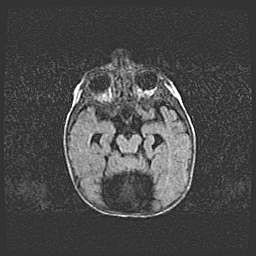

Церебральная ишемия II.

Возраст: 5 дней

Вес: 3400 г

Пол: женский

Окружность головы: 35 см

Срок гестации: 39 недель

Церебральная ишемия – это заболевание, характеризующееся недостаточностью (гипоксией) либо полным прекращением (аноксией) снабжения мозга кислородом по причине закупорки одного или нескольких сосудов. Это приводит к  что метаболическим расстройствам различной степени тяжести в тканях головного мозга, развитию коагуляционных некрозов и гибели нейронов.